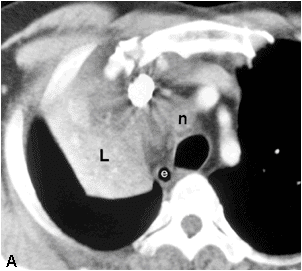

Enhancing right upper lobe collapse with sharp margins delineated laterally with minor fissure and posteriorly with major fissure.

Evidence of volume loss in the right hemithorax.

obstruction in the lobar bronchus is demonstrated(black arrow).

n=mediastinal lymphadenopathy

black arrow head=compressed superior vena cava

white arrows=collapsed right upper lobe

black arrow=obstructed upper lobe bronchus.